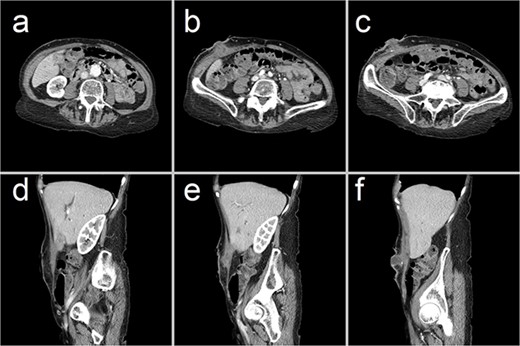

She represented 10 weeks later, complaining of pain at the previous surgical site. Remarkably, removal of the overlying wound dressing revealed a 20 mm gallstone lodged at the external opening of a CCF that had, by then, epithelialized along the previous drain tract (Figs 2 and 3). This obstructing gallstone and multiple others were removed from the visible fistula tract at the bedside using forceps.

Representative CT images showing (a–c) axial and (d–f) sagittal views of the CCF, forming a communicating tract that extends from the gallbladder fundus, through the anterior abdominal wall and onto the skin. There has been interval collapse of the gallbladder, whose wall remains thickened with mucosal hyperenhancement, in keeping with chronic cholecystitis. Hyperenhancing gallstones are visible along this fistula tract.